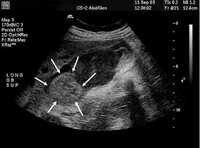

Gallbladder ultrasound of mass (arrows)

From the collection of Dr Joseph Espat; used with permission